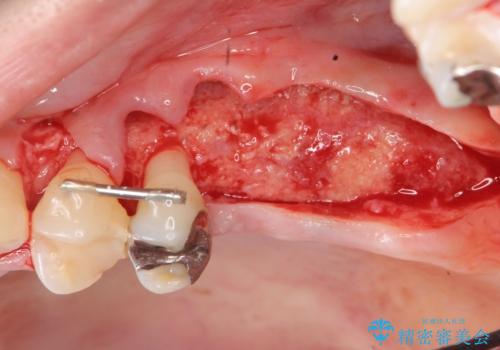

X線検査の結果、左上6には歯根破折、左上7には銀歯の下に大きな虫歯の再発が認められ共に抜歯をせずには症状の改善が見込めない状況です。

奥歯を2本失ったのち、しっかりと噛める環境へと整備するため、しっかりと骨の造成を行い清掃性を高めたインプラント治療を行っていくこととしました。

インプラントの仕上がりを見越して、ただ埋入するだけではなく長期的な予後を見込むには清掃のしやすい環境を整備することが大切です。

今回は大きく吸収してしまった歯槽骨をしっかりと造成することで、歯間ブラシを行いやすいインプラント周囲環境を整備することができました。